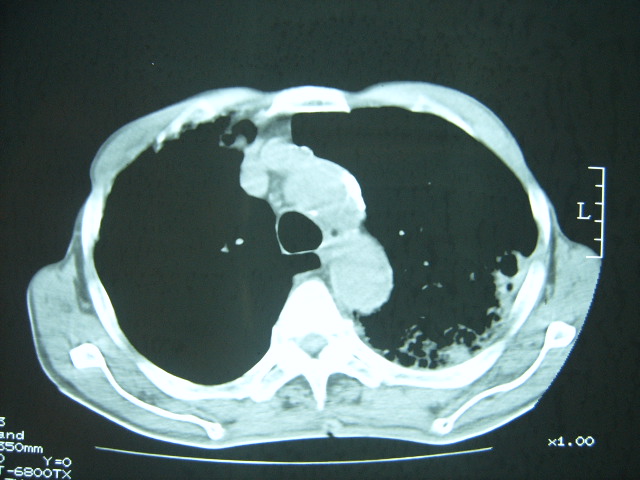

男74岁,咳嗽,寒战,低烧。有糖尿病史。

两肺结核,空洞形成,左下肺肺段隔离症待排

1、左下肺肺脓肿,合并霉菌球形成?.2、双肺陈旧性病灶.3、右上肺病灶警惕瘢痕癌,建议定期复查.

两肺结核,左下肺大片实变,内见空洞性病变,壁不规则,结合糖尿病史,考虑:结核性?霉菌性?建议结合实验室检查或治疗后复查。